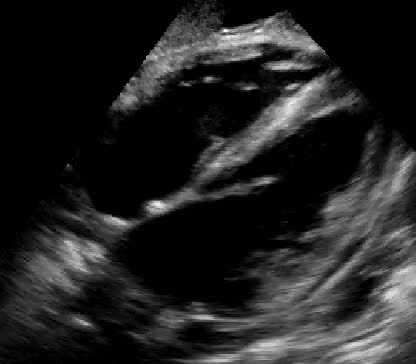

Titolo:

Stenosi mitralica

Autore:

Chiara Bencini